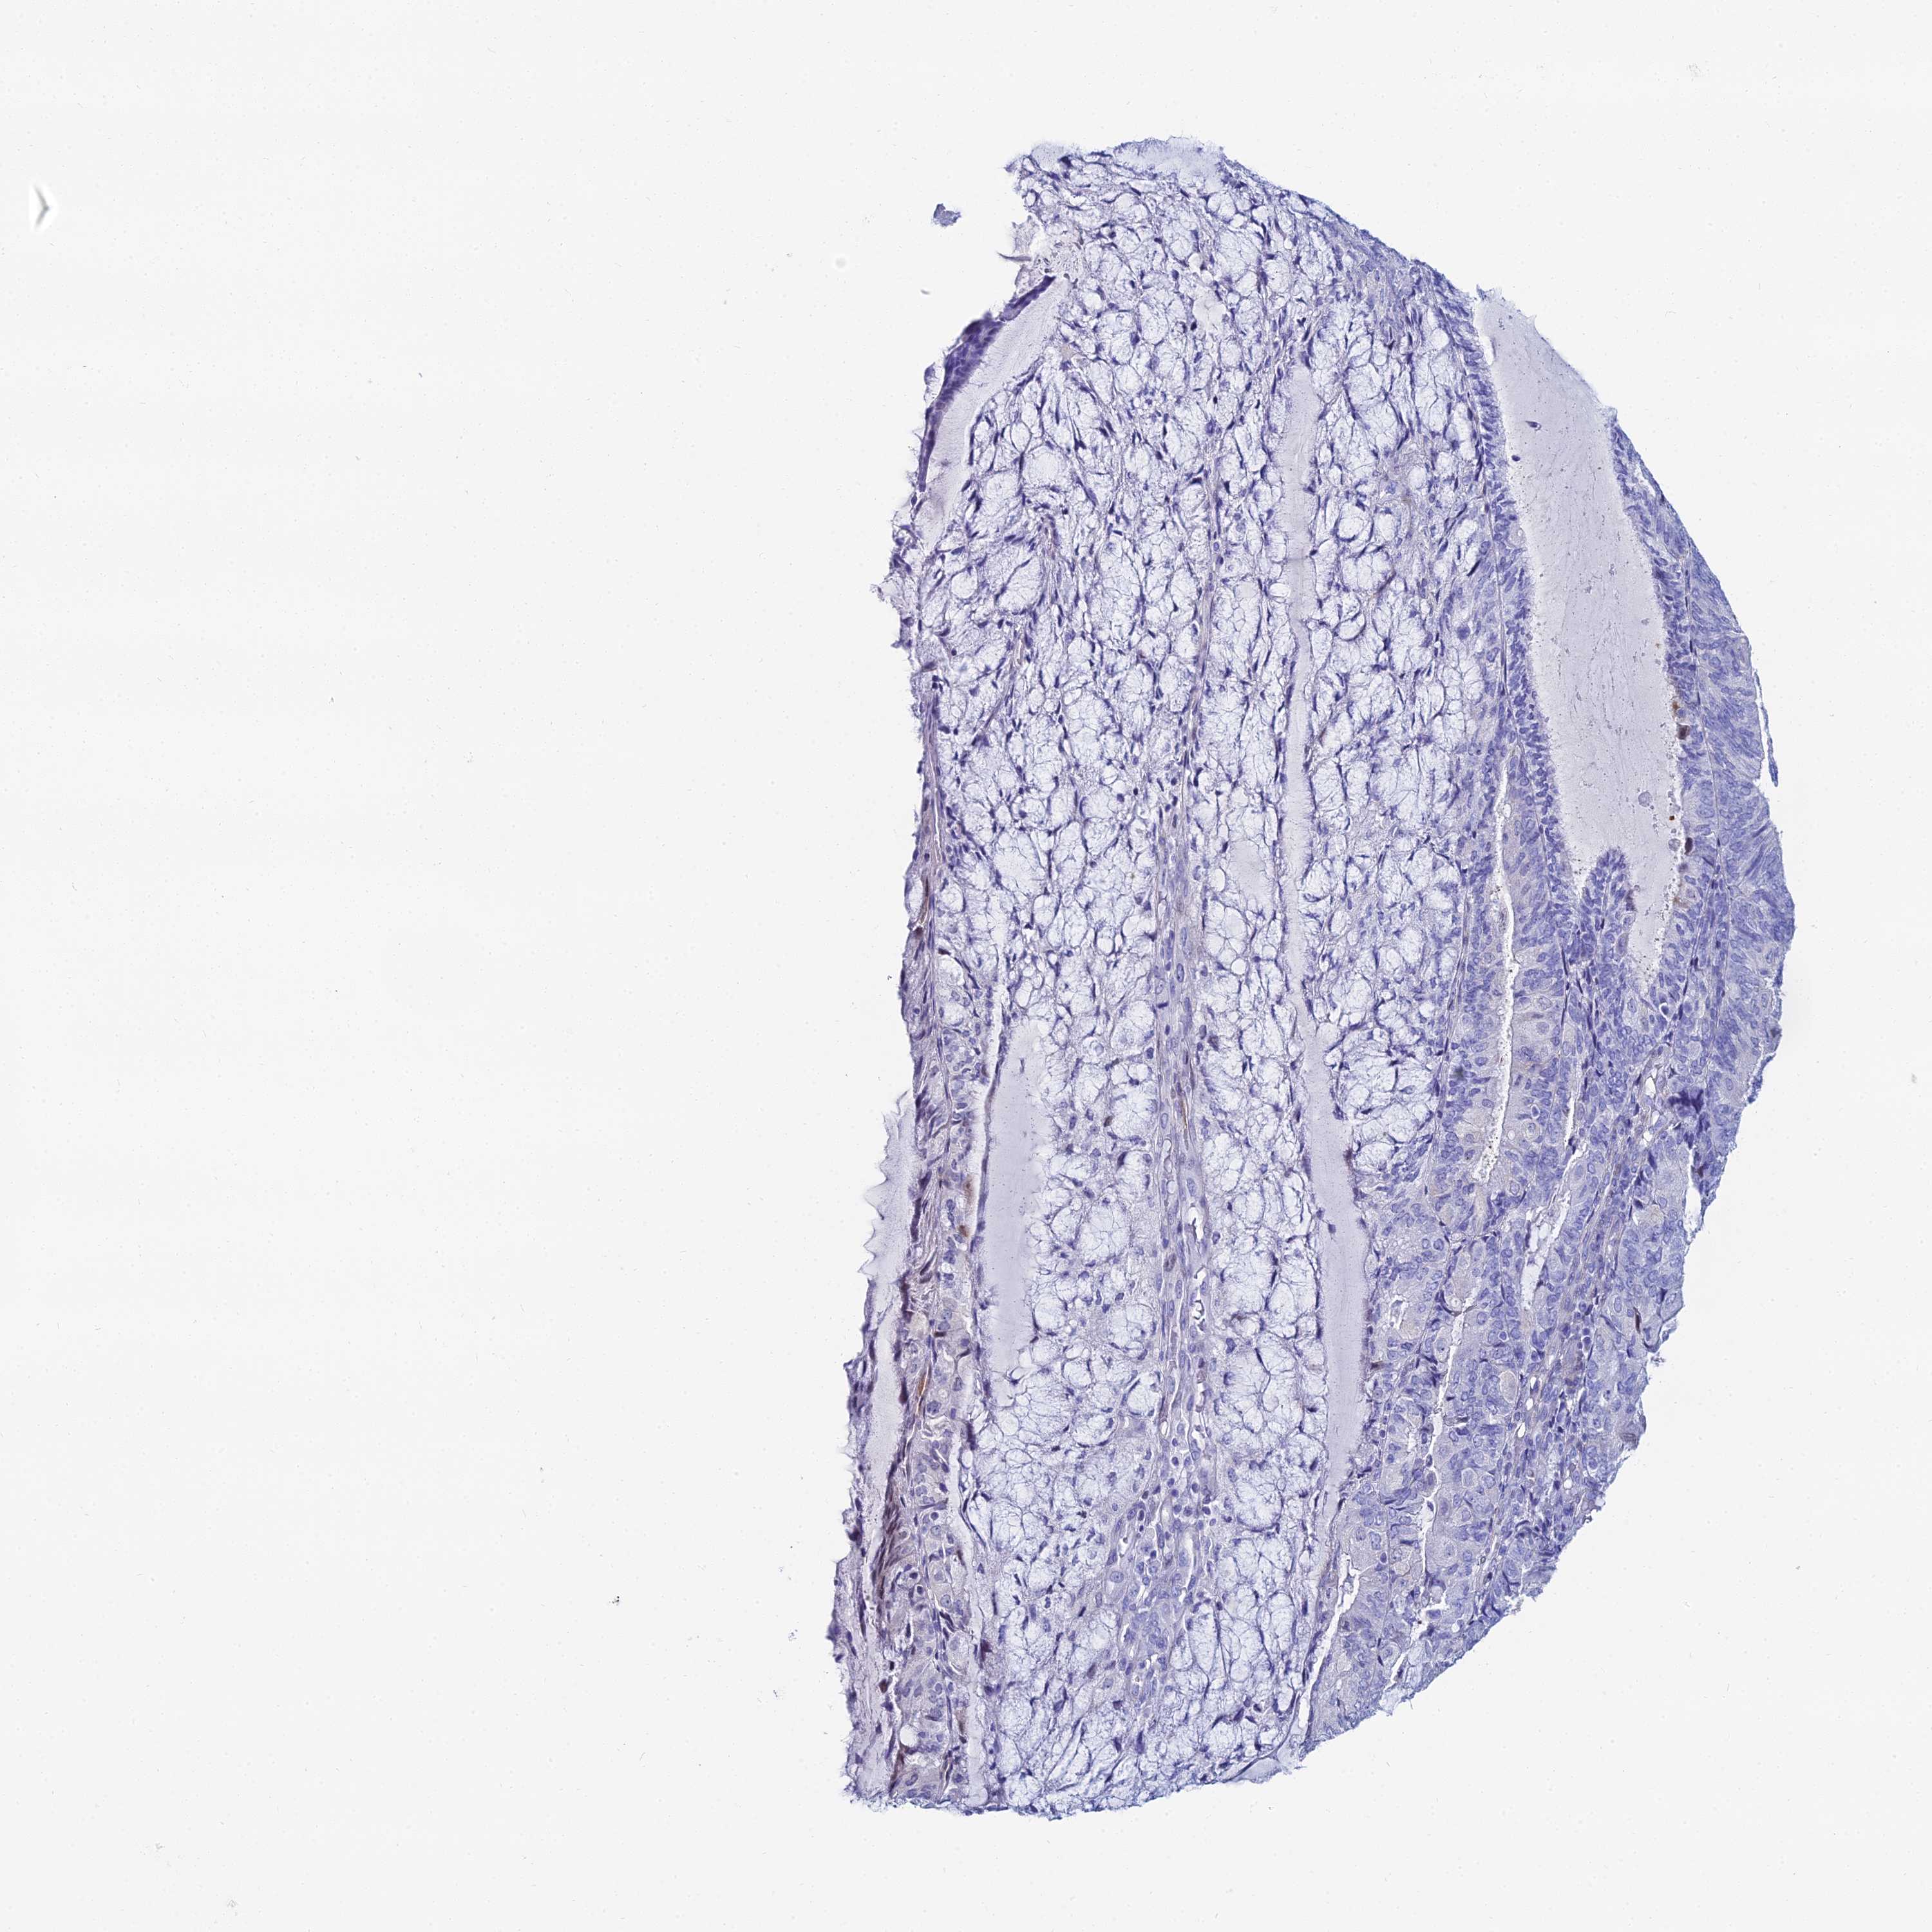

ENDOMETRIAL CANCER - Protein expressioni

A mouse-over function shows sample information and annotation data. Click on an image to view it in a full screen mode. Samples can be filtered based on level of antibody staining by selecting one or several of the following categories: high, medium, low and not detected. The assay and annotation is described here.

Note that samples used for immunohistochemistry by the Human Protein Atlas do not correspond to samples in the TCGA dataset.

Antibody stainingi

Antibody staining in the annotated cell types in the current human tissue is reported as not detected, low, medium, or high, based on conventional immunohistochemistry profiling in selected tissues. This score is based on the combination of the staining intensity and fraction of stained cells.

Each image is clickable and will lead to virtual microscopy that enables deeper exploration of all samples and also displays staining intensity scores, fraction scores and subcellular localization as well as patient and tissue information for each sample.

Antibody HPA043285

Antibody HPA052504

Staining

High

Medium

Low

Not detected

Intensity

Strong

Moderate

Weak

Negative

Quantity

>75%

75%-25%

<25%

None

Location

Nuclear

Cytoplasmic/membranous

Cytoplasmic/membranous,nuclear

Adenocarcinoma, NOS

Adenocarcinoma, metastatic, NOS

Carcinoma, NOS